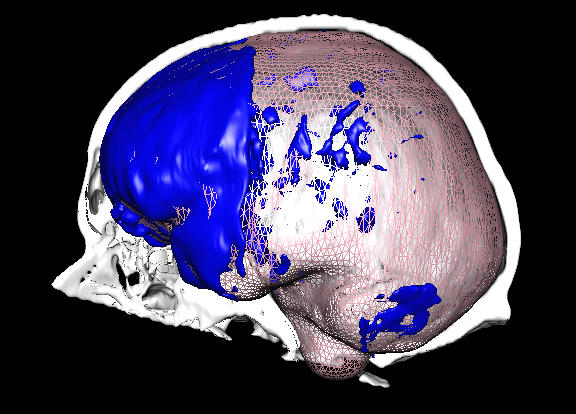

Automatische Erkennung des Acetabulum in 3D-Pelvis Modellen

Hüftimplantate zählen zu den häufigsten orthopädischen Operationen. Für eine patientenindividuelle Planung von Implantat und Eingriff ist es notwendig, sowohl die Hüfte (Pelvis) als auch den Oberschenkelknochen (Femur) zu identifizieren. Von besonderem Interesse ist dabei die Kontaktregion, die aus dem Kopf des Femur (caput ossis femoris) und der Hüftpfanne (acetabulum) besteht.

Ziel dieser Arbeit ist es, das Acetabulum in gegebenen 3D-Pelvis Modellen zu identifizieren. Dafür sollen unterschiedliche Algorithmen untersucht, implementiert und verglichen werden. Betreuer: Karl-Ingo Friese Mai 2014